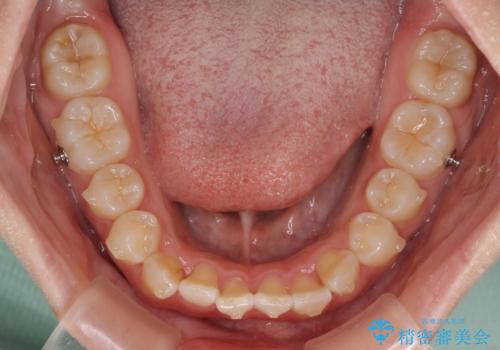

- 上下前歯のデコボコを気にして来院された患者様です。

叢生は軽度であり、ワイヤー矯正でもマウスピース矯正でも対応可能であったので、好きな装置を選んでもらいました。

相談の結果、インビザラインによる矯正治療を行うこととしました。

毎日の装着時間をしっかりと守っていただいたことで、1年程度で無事に治療を終えることができました。